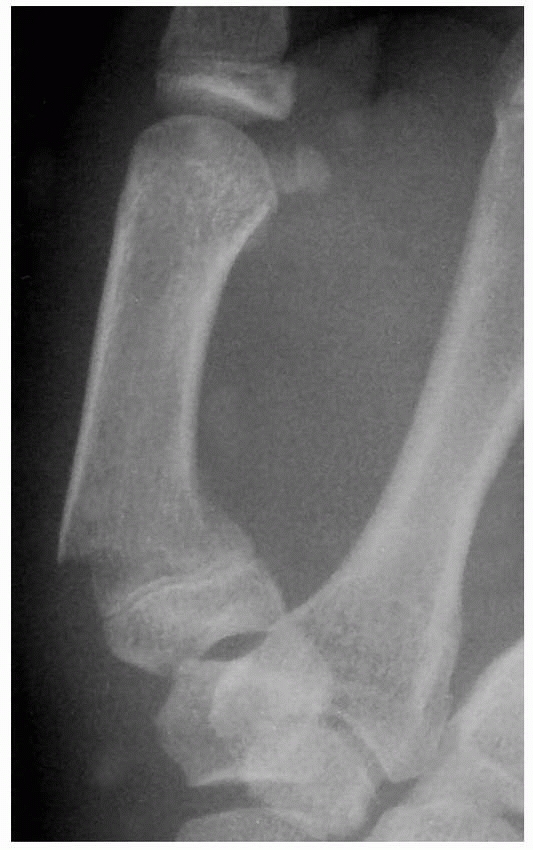

![]() |

FIGURE 8-38 A. A 14-year-old girl with incipient malunion of right thumb proximal phalanx neck fractures that impede flexion. B. Lateral radiograph reveals loss of the subchondral fossa. (continues)

FIGURE 8-38 (continued) C. Anteroposterior view after open reduction and Kirschner-wire fixation. D. Oblique view reveals restoration of subchondral fossa. E,F.